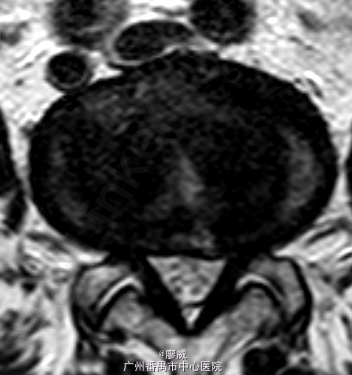

主诉:腰痛2年余,左小腿外侧麻痛半月。 病史:男性患者,52岁。患者2年前在做体力活时出现腰部剧烈疼痛,当时腰部活动受限,在外院门诊诊断为腰肌劳损,给予对症治疗,效果较好。2年来活动后腰部均出现疼痛,反复出现。最近半月以来,患者腰部疼痛时间延长,加重,并伴左小腿外侧麻木,放射痛至足踝处。患者一般情况尚可。

体查:左小腿外侧区域感觉减退;左侧直腿抬高试验50°(+),其余未见明显异常。 辅助检查:三大常规、血生化、肝肾功能均未见明显异常。患者腰椎动力位片正常,其余重要腰椎影像学如下。

目前诊断:腰椎间盘突出症。 处理:入院后完善相关检查,术前给予对症治疗,科里术前讨论决定:拟行手术:椎间孔镜下L4/5椎间盘摘除+椎间孔扩大成形+射频消融术。

讨论:该患者在影像学上看有多个节段的腰椎间盘突出,但最严重的是L4/5,结合患者临床症状及体查,主要也是L4/5。这虽然术后的情况说不定,也许完全缓解,也许还残留其他节段存在的问题。